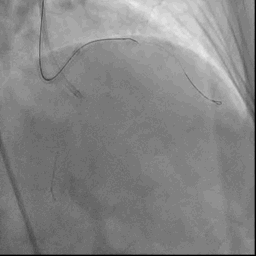

葛雷教授手术现场